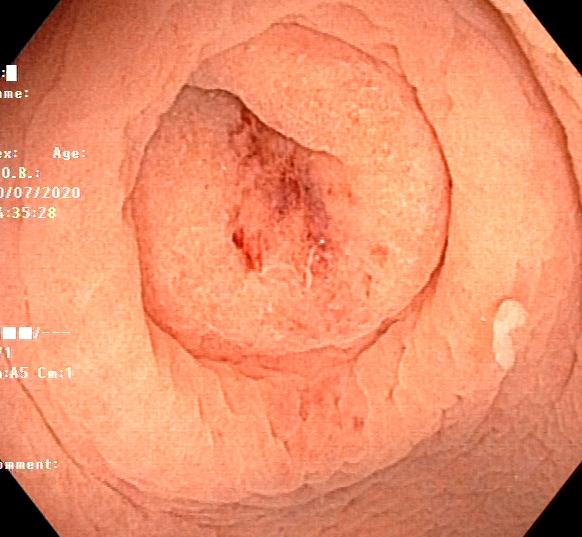

阑尾内口

然后下一步就阑尾口插管给它冲洗,冲出来很多的浓苔样的物质以及粪石,为了不影响大家心情,因此冲洗时候的视频就没有录制。

水下再观察一下干干净净的阑尾开口是不是很nice!